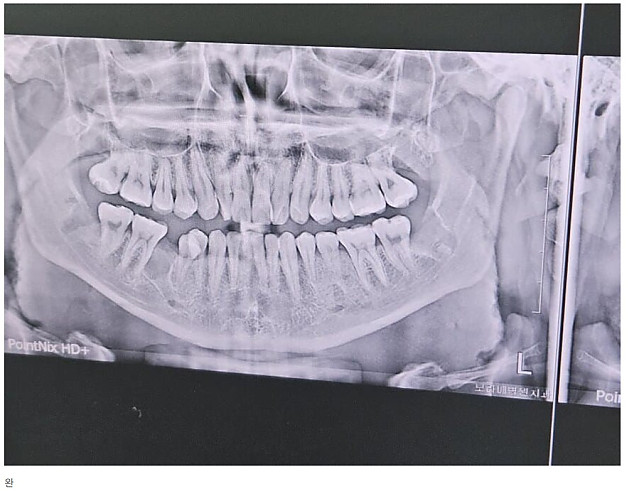

어느 사랑니갤러리의 사랑니 작성자 정보 붐붐의민족 작성 작성일 2025.01.25 01:57 컨텐츠 정보 16,264 조회 목록 본문 이걸 해내네.. 관련자료 링크 https://www.hafline.co.kr/bbs/board.php?bo_table=KA_3101&wr_id=1514 1365 회 연결 댓글 0 등록된 댓글이 없습니다. 로그인한 회원만 댓글 등록이 가능합니다. 목록